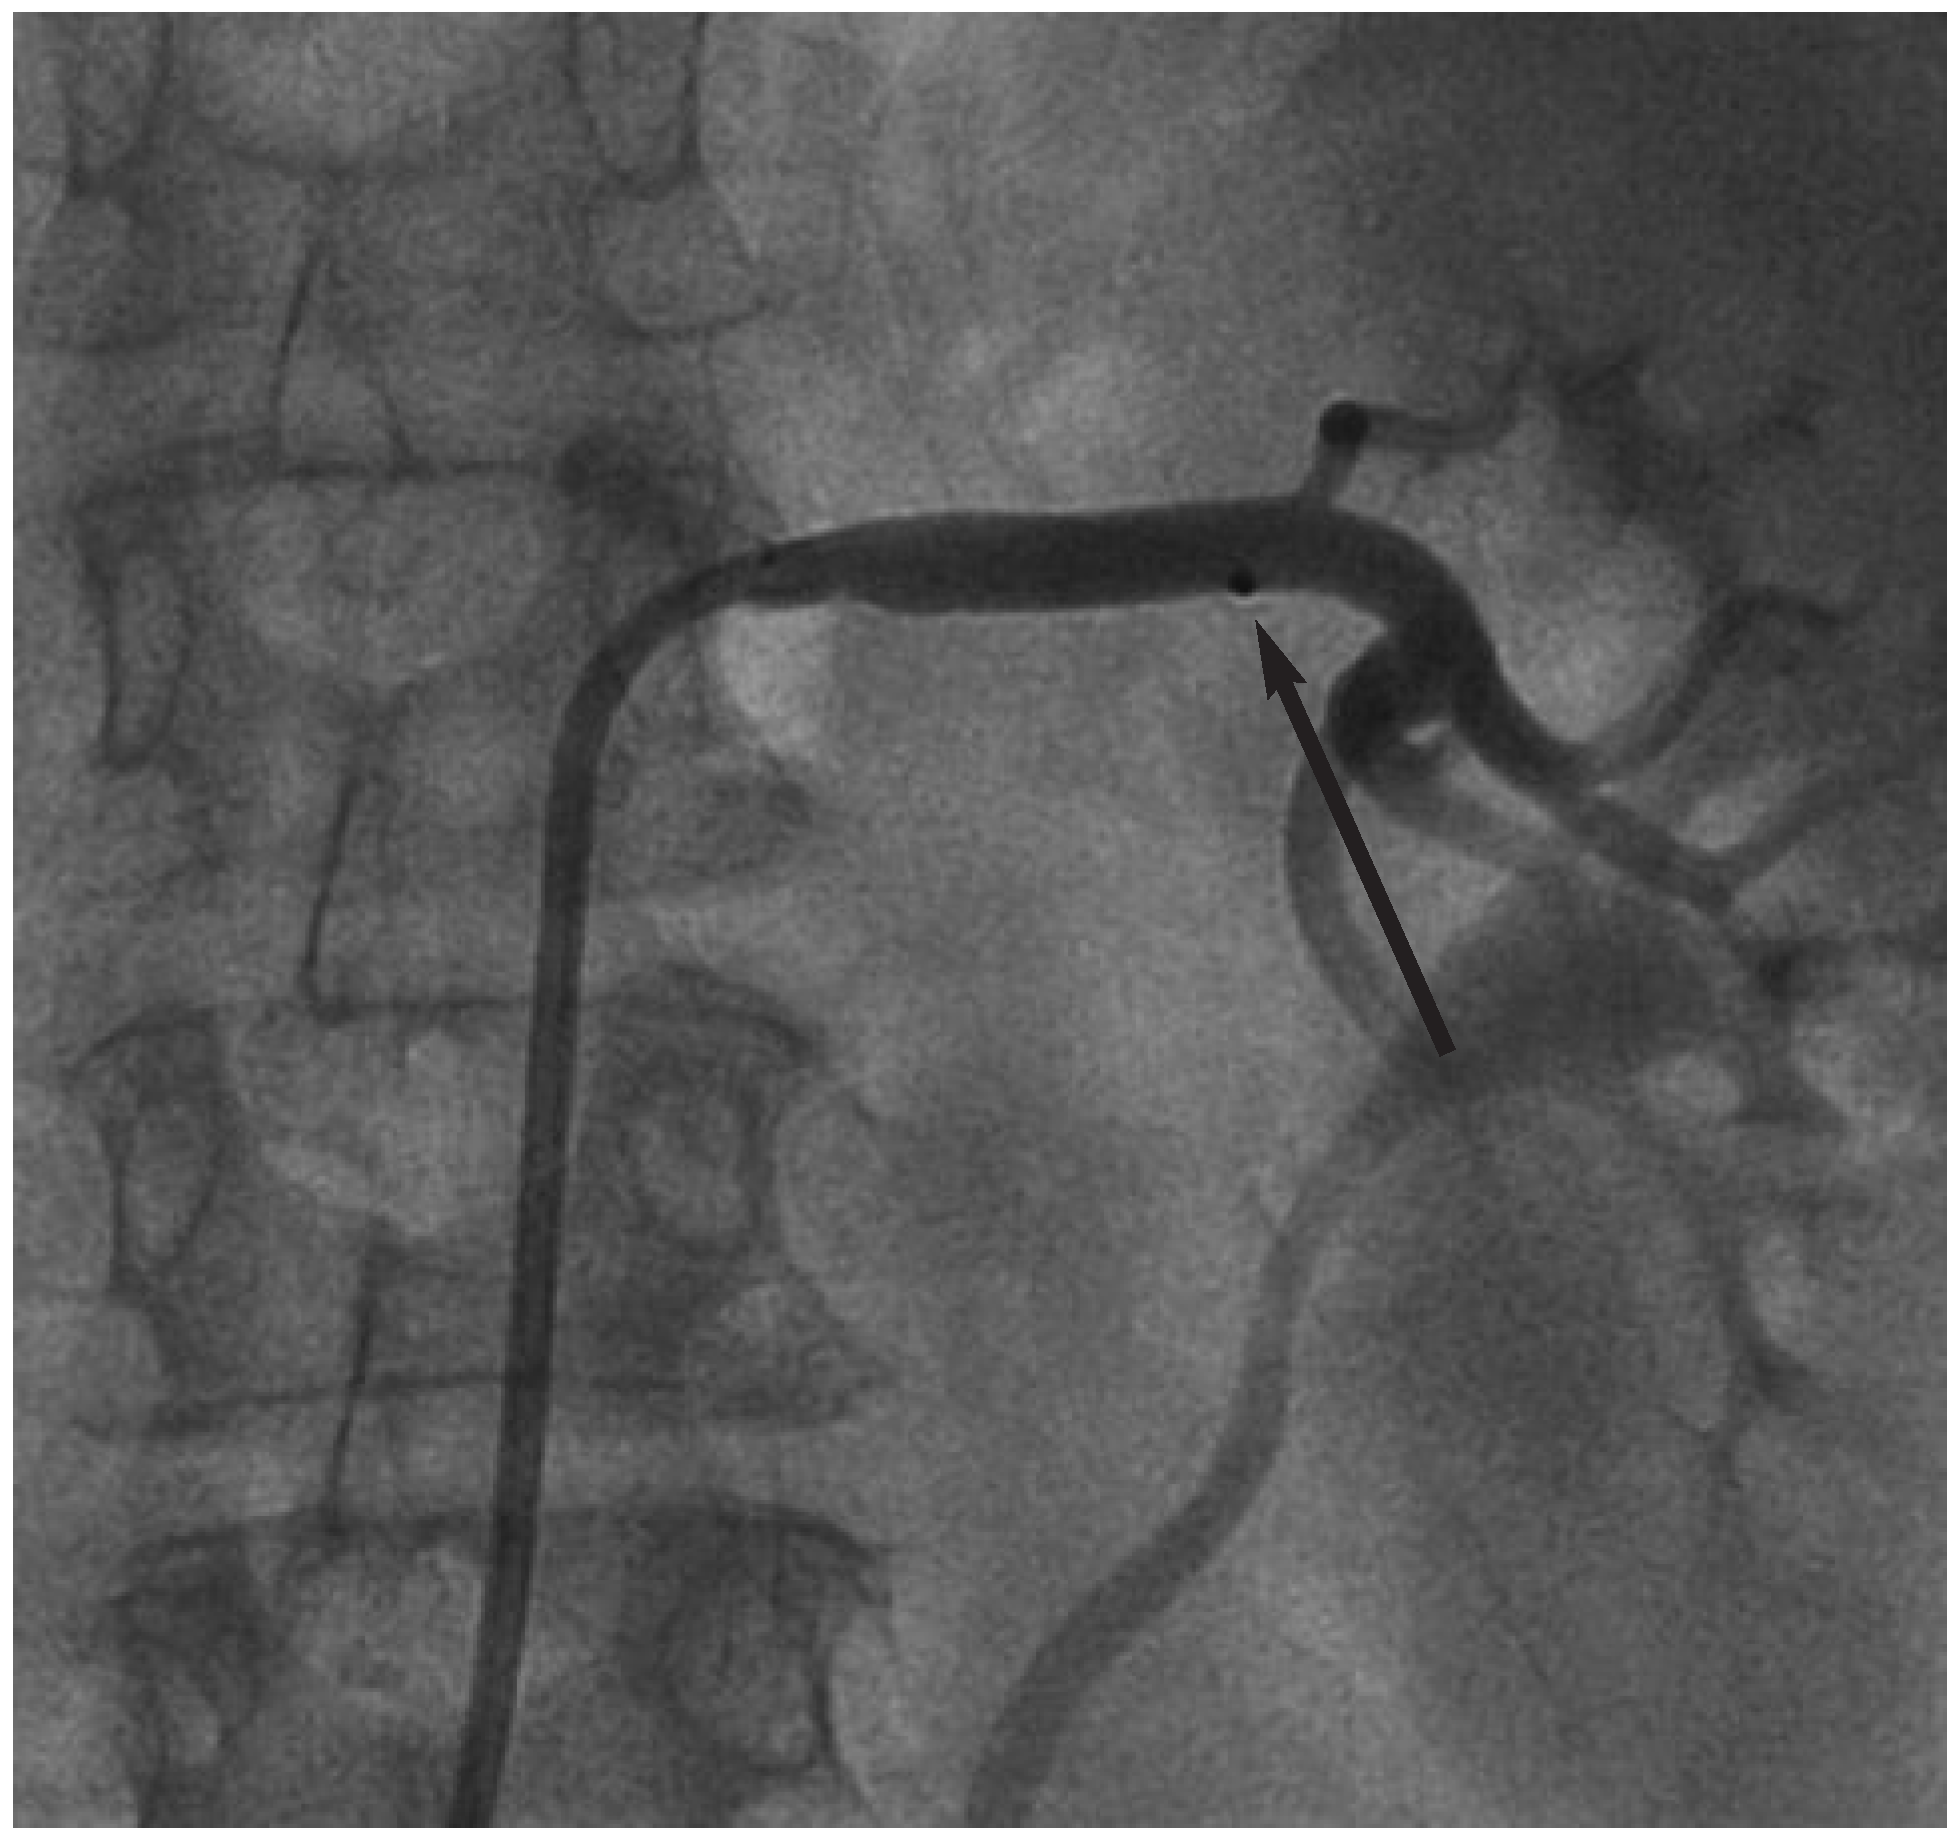

Abbildung 4.

Positionierung des Symplicity™-Ablationskatheters vor der ersten Ablation.

Abbildung 5.

Rückzug des Ablationskatheters nach erfolgter erster Ablation. Beachte «Ablations-Notch» (Pfeil) in Projektion auf die erste Ablationsstelle.

Zur Bereitstellung der Hochfrequenzenergie stand ein spezieller Generator (Symplicity™-Generator, Ardian, CA, USA) zur Verfügung, der nun mit dem Ablationskatheter verbunden wurde. Im Anschluss erfolgte die schrittweise Ablation der rechten Nierenarterie an 5 verschiedenen Positionen. Hierzu wurde an in Abbildung 4 ersichtlicher Position die erste Ablation erfolgreich durchgeführt. Im Anschluss wurde der Ablationskatheter um 5 mm zurückgezogen (Abb. 5) und eine weitere Ablation durchgeführt. Die folgenden Ablationen wurden nach gleichem Muster ausgeführt. Nach erfolgreicher Ablation der linken Nierenarterie konnte angiographisch eine Dissektion oder eine relevante Stenosierung der Nierenarterie ausgeschlossen werden (Abb. 6). Nun erfolgte ebenfalls die Ablation der rechten Nierenarterie identisch den vorher beschriebenen Schritten.